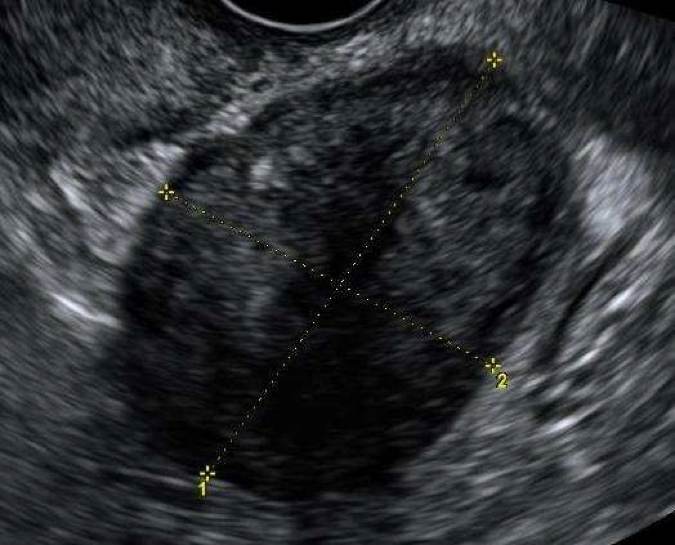

Granulosacellstumörer producerar ofta östrogen och förekommer hos kvinnor i alla åldrar. I en serie på 23 fall beskrivs tumören som ensidig, solid eller flerrummigt solid (många gånger solid med små cystiska hålrum, s.k. ”schweizerost”). Den har rikligt blodflöde och oregelbunden ekogenicitet med en medeldiameter på 10 cm3. Se bild 5.

Bild 5. Granulosacellstumör hos 30-årig kvinna med blödningsrubbningar och infertilitet.